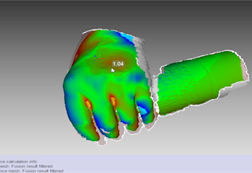

改良された偏差、設計、許容度確認機能により品質を保証

メッシュとCADの最大偏差も設定できるようになった、Artec Studioの改良された3D比較マップ(Enhanced 3D Compare Map)を用いて品質保証(Quality Assurance、QA)を行うことで、誤差の確認も更に迅速に行えます。Artec Studioで初めて導入された厚さマッピング(Thickness Mapping)や許容度確認モード(Tolerance Check Mode)も、モデルを業界基準に確実に適合させるために役立ちます。

2. 手の”むくみ”を診断する。むくみ・ある/なしの状態を1ミリ精度で表現する。